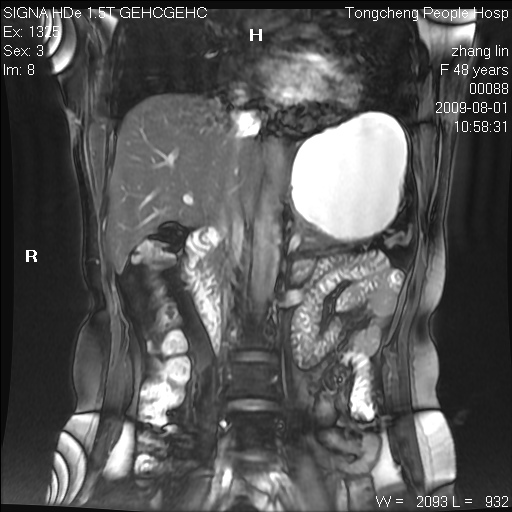

女,48岁。健康体检,彩超发现右肾占位性病变。平素健康。

临床诊断:右肾占位性病变,性质待定(囊肿?肿瘤?)。

上中腹部mr平扫+增强扫描,图像如下:

右肾上极见一类圆形病灶,t1wi呈等信号t2wi呈等高混杂信号,三期增强无强化,边界清---考虑囊肿出血。

肝囊肿

慢性胆囊炎